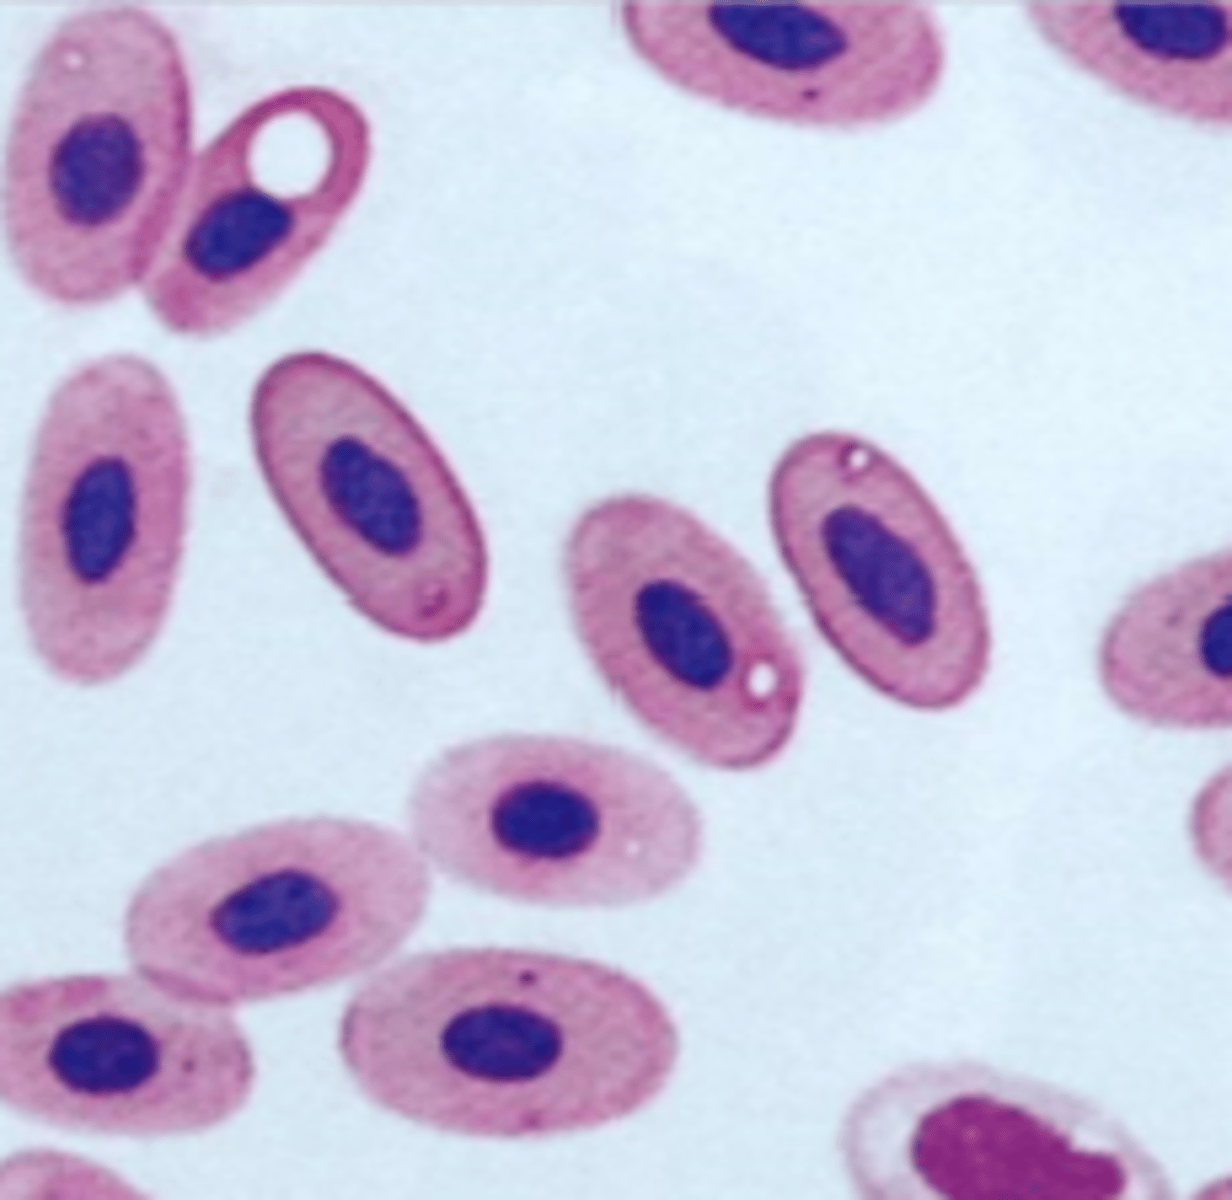

erythrocyte

avian or reptile

organelle breakdown artifact on exotic RBC

exotic

hint: not clinically significant

degenerative organelle artifact on exotic RBC

exotic

small punctate, variably sized, clear vacuoles that are not clinically significant